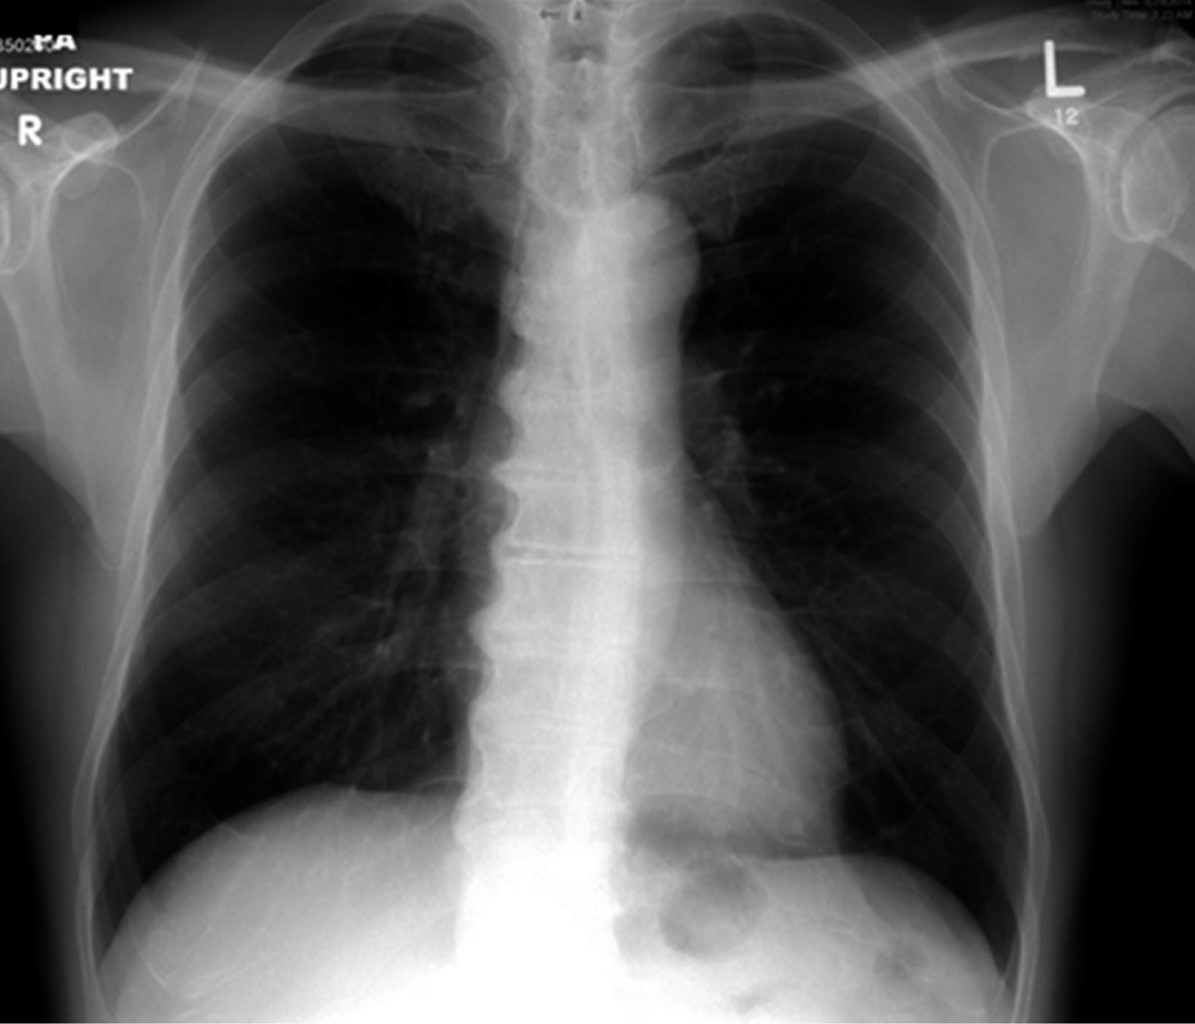

Los aneurismas del seno de Valsalva son dilataciones congénitas o adquiridas de la pared del seno aórtico a nivel justo por encima de las tres cúspides de la válvula aórtica, que pueden ser casos asintomáticos o fatales si se rompen, más frecuentemente hacia las cavidades cardiacas derechas. Estos casos son relativamente raros. Presentamos el caso de un varón de 72 años remitido por sospecha de soplo pulmonar. La evaluación reveló un aneurisma del seno de Valsalva derecho, que causaba compresión del tracto de salida del ventrículo derecho (TSVD). El ecocardiograma, la tomografía computarizada y el aortograma revelaron imágenes interesantes y evocadoras. El paciente recibió una reparación quirúrgica mid-cap. Este artículo revisa y discute la literatura actual y presenta el caso.

Figura 3